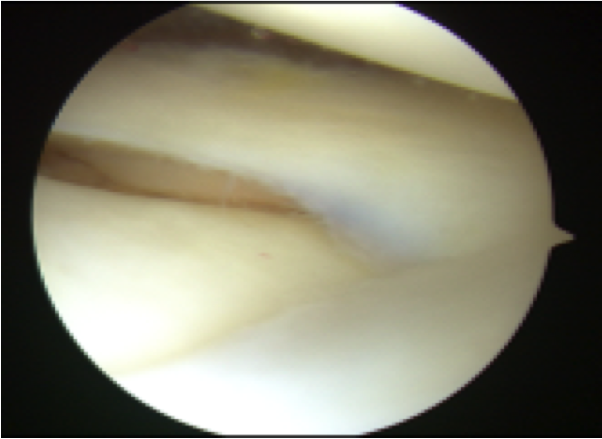

ACLは大腿骨付着でわずかに

残存するも、緊張は認めず

機能していない